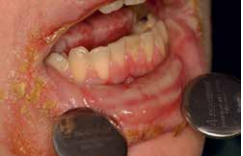

HIPERPLAZIJA GINGIVE

Prilično česta i poznata neželjena nuspojava uzimanja antihipertenziva (blokatori kalcijevih kanala; nifedipin), antiepileptika (fenitoin) i imunosupresiva (ciklosporin) je hiperplazija gingive koja obično nastaje nekoliko mjeseci nakon uzimanja ovih lijekova. Hiperplazija se pogoršava neodržavanjem oralne higijene pa se u ovih pacijenata preporučuju češće kontrole kod stomatologa. Ukoliko je jako izražena hiperplazija gingive kao u slučaju na slici vrlo često je potreban kirurška obrada gingive tzv. gingivektomija.